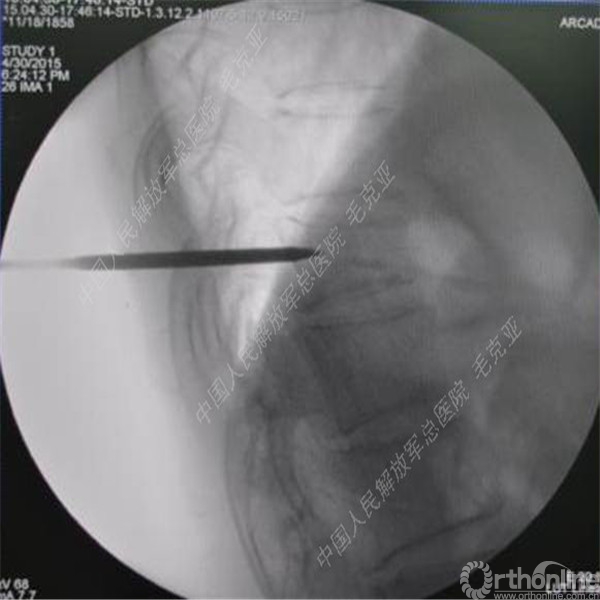

导语:随着社会老龄化的不断加速,骨质疏松性椎体压缩骨折作为一种普遍存在的老年骨科疾病已经成为现今骨科界的一个热点话题。传统的保守疗法治疗效果不佳,而现有的椎体增强技术又具有多种风险和缺陷。针对这种现状,中国人民解放军总医院毛克亚教授提供了一种新的解决方法。